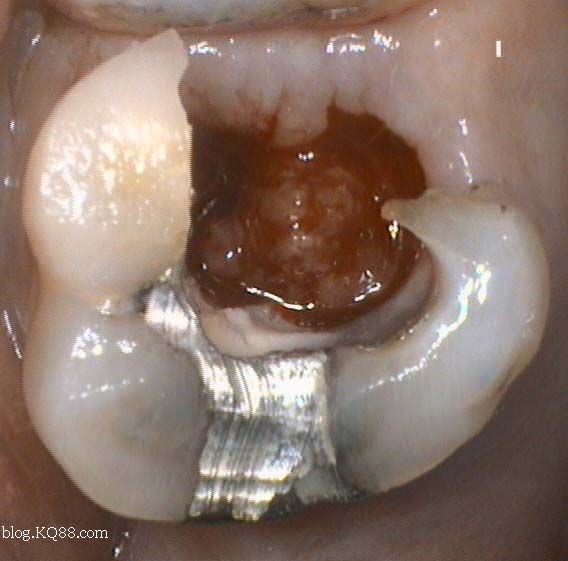

1、口腔鏡檢查:通過口腔鏡檢查,可以清晰地觀察到牙齒表面的牙洞以及牙洞內(nèi)的情況,醫(yī)生可以判斷牙洞是否已深入牙髓,并評估病情嚴(yán)重程度。

2、探診檢查:使用牙科探針檢查牙洞周圍組織的健康狀況,了解牙洞深度及與牙髓的關(guān)系。

X光檢查是判斷牙齒牙洞是否深入牙髓的重要手段之一,通過X光檢查,可以清晰地看到牙齒內(nèi)部結(jié)構(gòu),了解牙洞的位置、大小及深度,從而判斷牙洞是否已侵犯到牙髓。